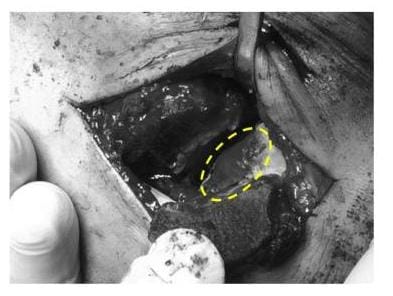

Das Bild zeigt einen OP-Situs. Das Sprunggelenk ist über eine Innenknöchelosteotomie eröffnet. Der geschädigte Gelenkbereich des Sprungbeines wurde mit Eigenknochen aufgefüllt und mit einer Kollagenmatrix bedeckt (gelbe Umrandung). (Bild: Orthopädie)